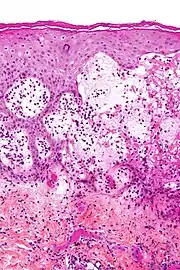

Penfigóide gestacional é uma dermatose da gravidez. É uma doença autoimune e bolhosa da pele que ocorre durante a gravidez, geralmente no segundo ou terceiro trimestre e/ou imediatamente após o nascimento. Era inicialmente denominada herpes gestacional devido à aparência semelhante, embora não tenha nenhuma associação com o herpesvírus.[1][2][3]